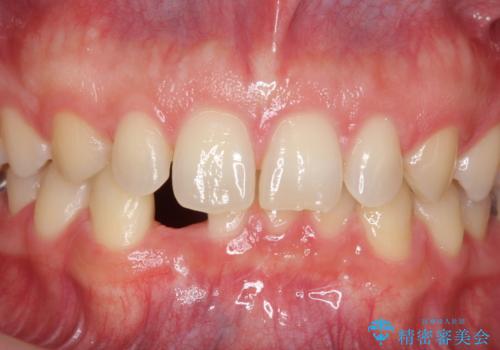

下の前歯のインプラント 生まれつき歯が少ない

- 下の前歯が1本生まれつき少なかったため、インプラント治療を行いました。

インプラントの前に矯正治療を行い、入れる隙間を確保しました。

ブリッジにすることも可能でしたが、両側の歯が天然歯であること、また、事前に矯正で噛み合わせを整え、幅も確保していたこと、CTにより骨の厚みがある程度あったことを踏まえ、インプラントも可能であるとお話しし、選んでいただきました。